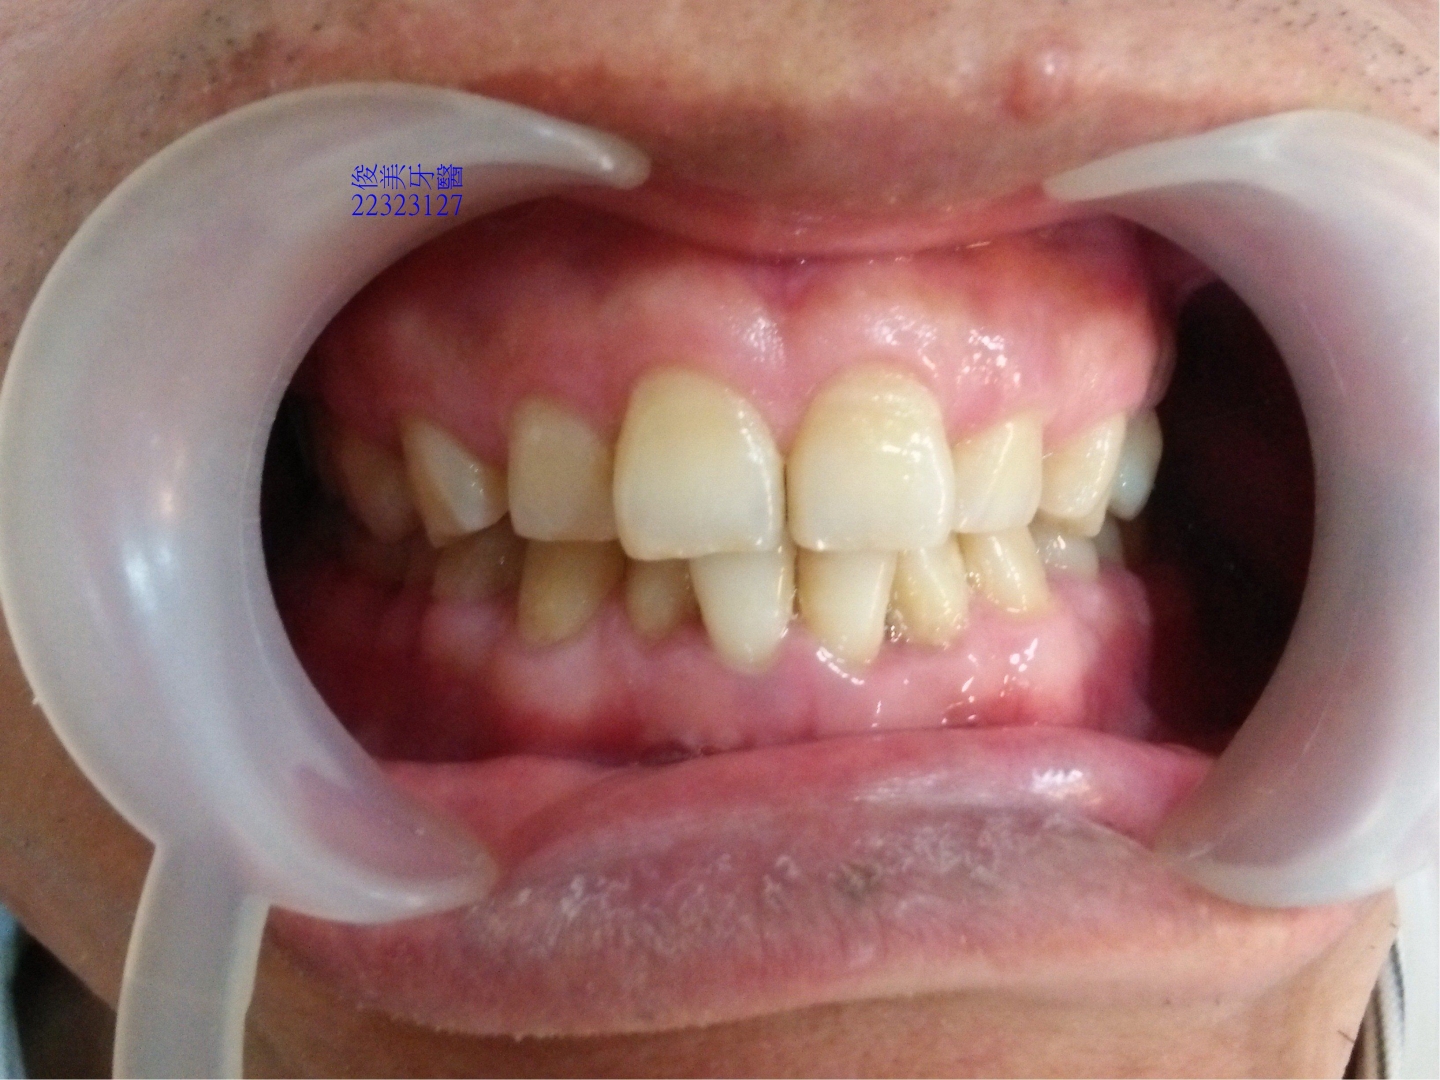

患者因牙齒過度磨損,缺牙未補,導致牙齒位移,牙弓明顯變形,咀嚼食物時牙縫會塞,牙齦經常發炎腫起來,

因此醫師分析後建議患者不可單純補缺牙,對整體問題無法改善,患者考慮後,因為經常發炎非常困擾,決定接

受醫師建議做整合性治療。

牙齒位移,前牙受力明顯過多,牙齒磨損的很平,牙齒變短、切端變厚。

牙縫開始變大。

咬合狀況。